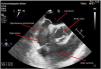

Patient admitted to the ICU due to SARS-CoV-2-induced pneumonia who required mechanical ventilation and was transferred to one of the hospital conventional wards after 14 days at the ICU treated with anticoagulant therapy with enoxaparin. He was readmitted due to respiratory failure. The CAT scan performed revealed the presence of thrombi in segmental arteries of both the right superior and left inferior lobes. The transesophageal echocardiogram performed revealed the presence of dense, spontaneous echocontrast in the right chambers (Appendix B; video 1 and Fig. 1). After the new hospital discharge, the patient showed low level of consciousness. The cranial CAT scan performed revealed the presence of an infarction at right medial cerebral artery level while the transesophageal echocardiogram performed revealed the presence of a coumadin ridge (variant of normality) with attached thrombotic material (Appendix B; video 2 and Fig. 2), and lack of cardiac shunt (Appendix B; video 3). A sequela of left residual hemiparesis remained at the ICU discharge. This is a clear example that the infection due to COVID-19 increases the risk of thromboembolic events.